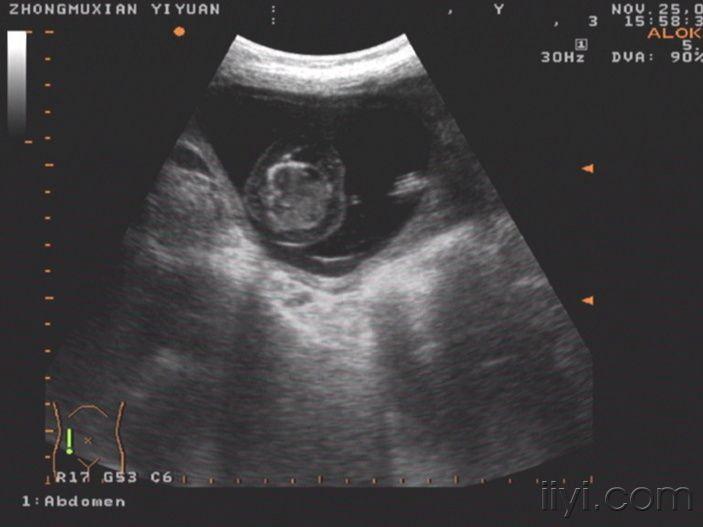

这个胎儿穿上了“太空衣”(典型胎儿水肿图片,值得分享!)

一位32岁经产妇,孕20周前来检查,发现胎儿被一层透明的膜状物包绕,从头颅到肢体,考虑胎儿水肿综合症!